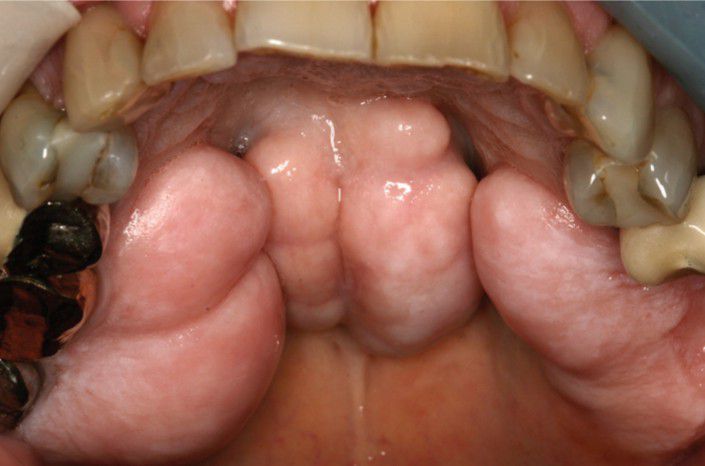

Palatal exostosis and torus palatinus

Massive bilateral palatal exostoses in a patient with a large palatal torus.